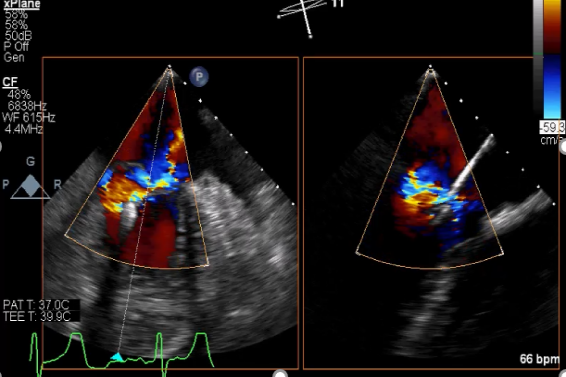

麻醉状态下TEE显示中大量返流MR:

患者麻醉方式采取全麻,建立静脉通路后,穿刺右侧股动脉以及股静脉,预埋ProGlide缝合器,冠脉造影复查提示支架通常。TEE超声指导下经房间隔穿刺后进入左房,送入鞘管,MitraClip调整后顺利到达二尖瓣目标位置,后在X线及食道超声辅助下,使用1枚XTR二尖瓣夹准确夹合二尖瓣A2-P2区,超声即刻测反流面积明显减少,LVOT切面,四腔心切面以及3D下证实夹合组织充分,患者收缩压由术前的108/62mmHg上升至130/72mmHg,左心房压力显著减低,肺静脉多普勒波形由反向恢复正常。手术顺利结束,安返普通病房。

术中超声引导过程

房间隔穿刺:

Bicaval 寻找穿刺点

穿刺点距离二尖瓣环3.42cm

二尖瓣联合部切面引导XTR夹子转向病变区域并逐渐进入左室

XTR夹子到达病变区域捕获瓣叶并逐渐夹闭

XTR夹子释放,返流明显减少

术后肺静脉频谱

二尖瓣瓣口面积及平均跨瓣压差评估(4mmHg)